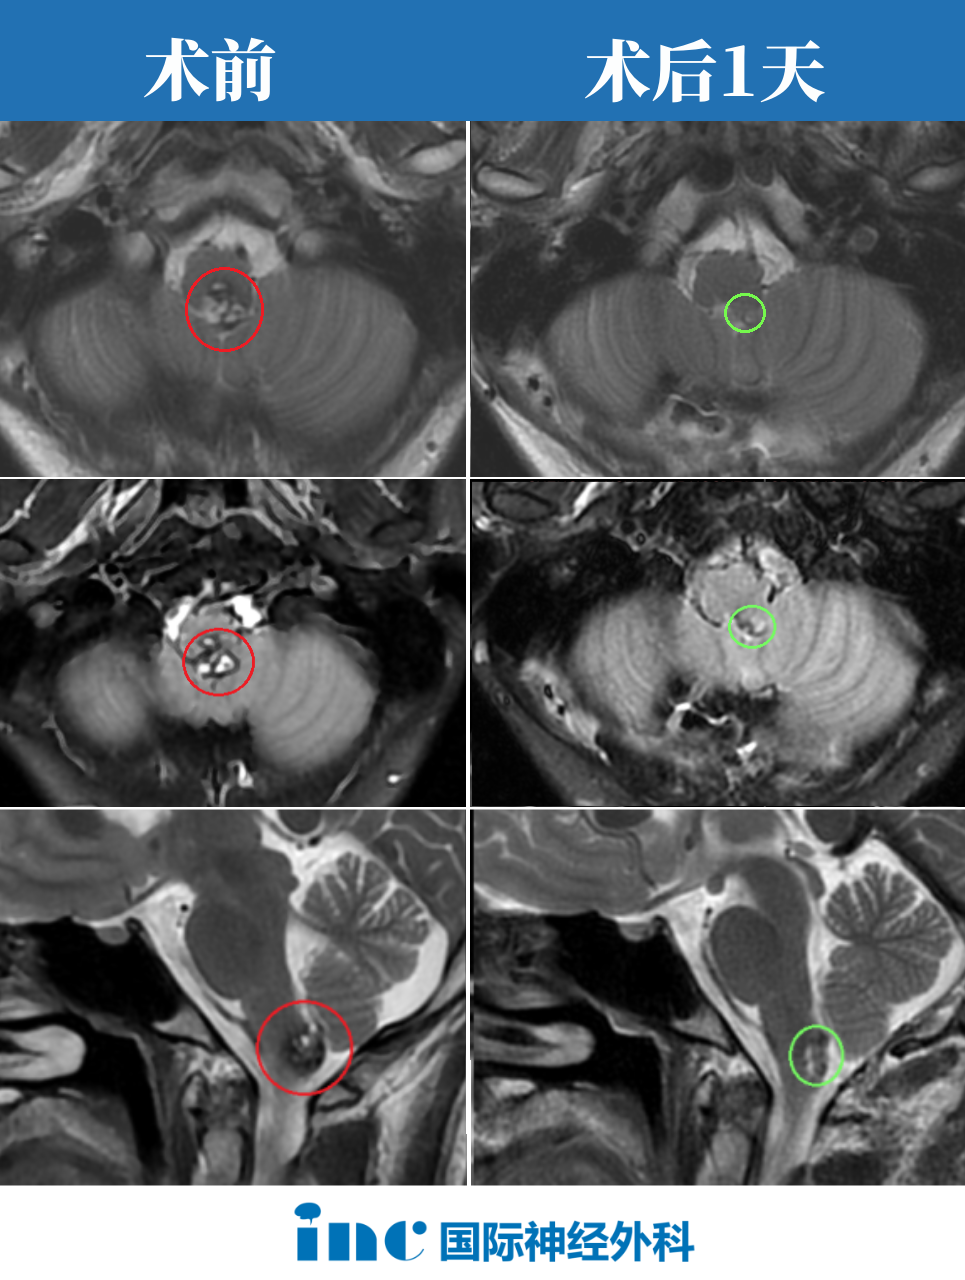

2022年11月27日,由巴特朗菲教授主刀,在国内神经外科团队的配合下阿朔延髓深处的海绵状血管瘤被成功完整切除。

- 术后第1天:阿朔意识清醒,四肢活动自如,顺利转出ICU。